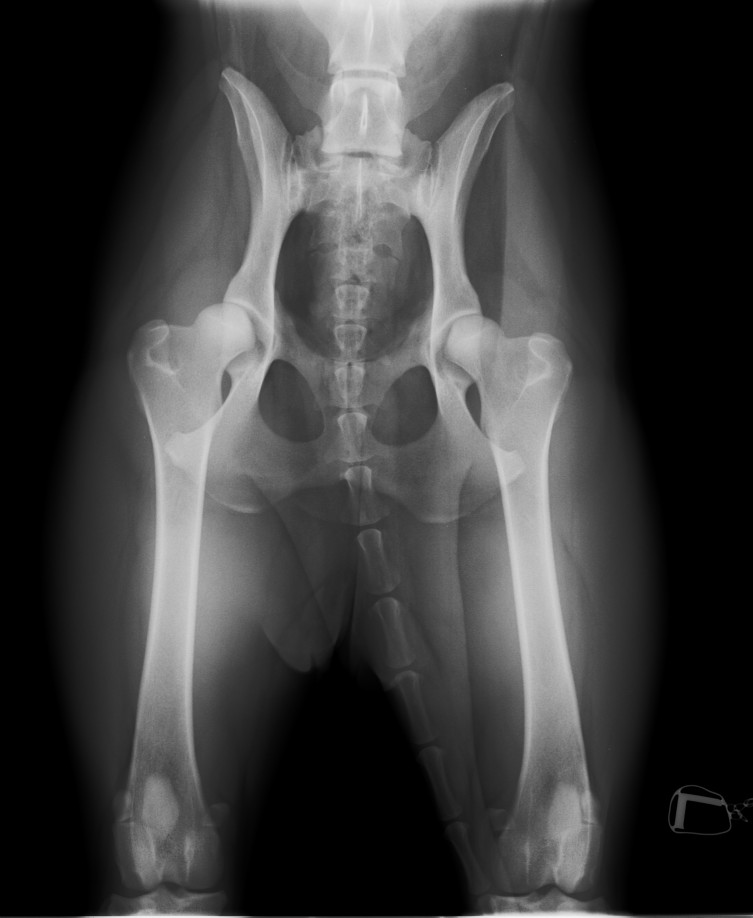

HD-Röntgen mit 8 Monaten, 2014, Dr. Eckes in Lindlar.

Ergebnis: nicht Top, aber brauchbar. Keine Probleme zu erwarten, auch wenn es besser sein könnte. Offizielle Zuchtzulassung: eher nicht - aber wollen wir sowieso nicht.